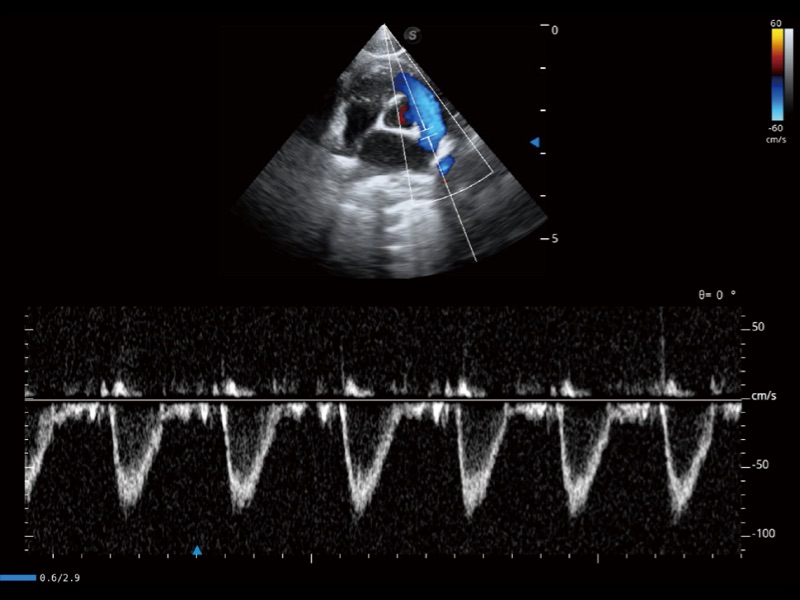

通过360度任意调节3条M型取样线,在同一心动周期上观察心脏不同位置的运动曲线,得到准确的心功能测量数据,有效评估心肌运动及左心室功能。

通过色彩血流和实时宽景相结合,可观察到完整的静脉或动脉的血流,方便医生检查。实时扫查过程中,如有任何操作失误也可以很容易地进行回扫擦除,而不会中断扫查。